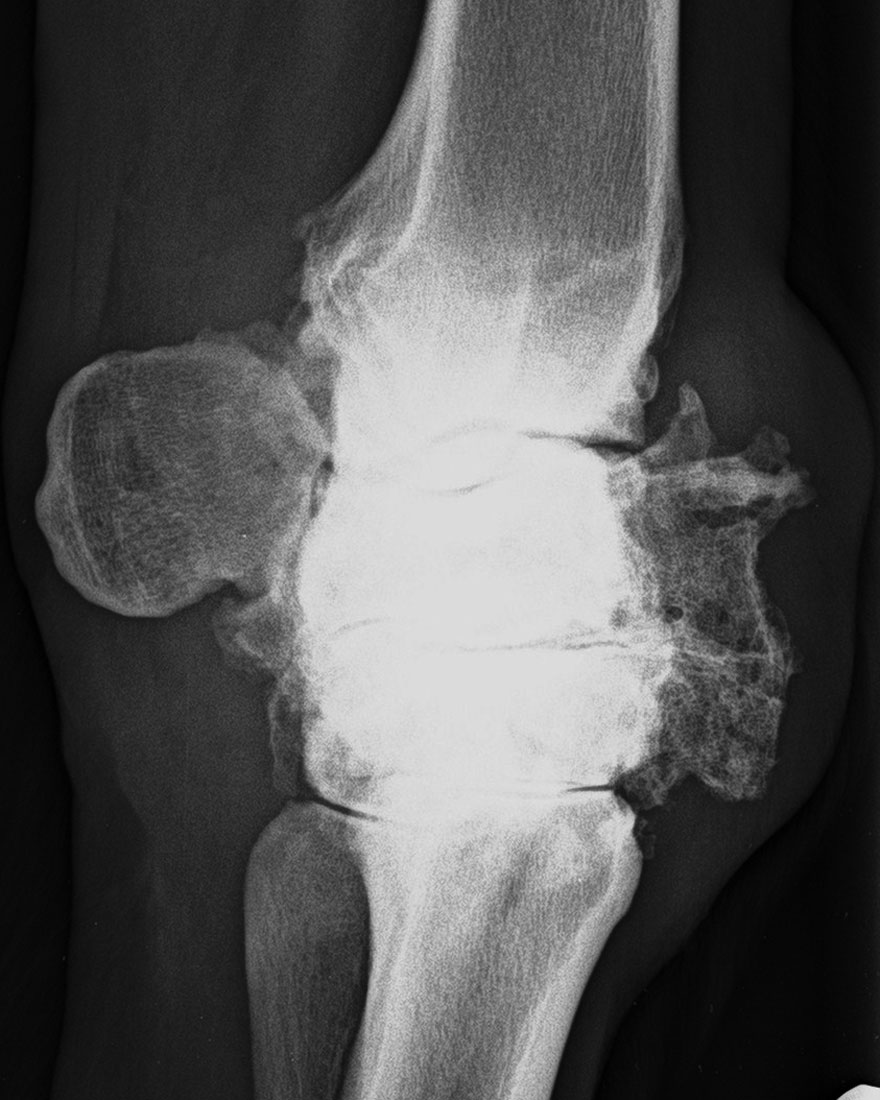

Höchstgradige Karpalgelenksarthrose mit weitgehender Ankylosierung (Versteifung) des Gelenkes